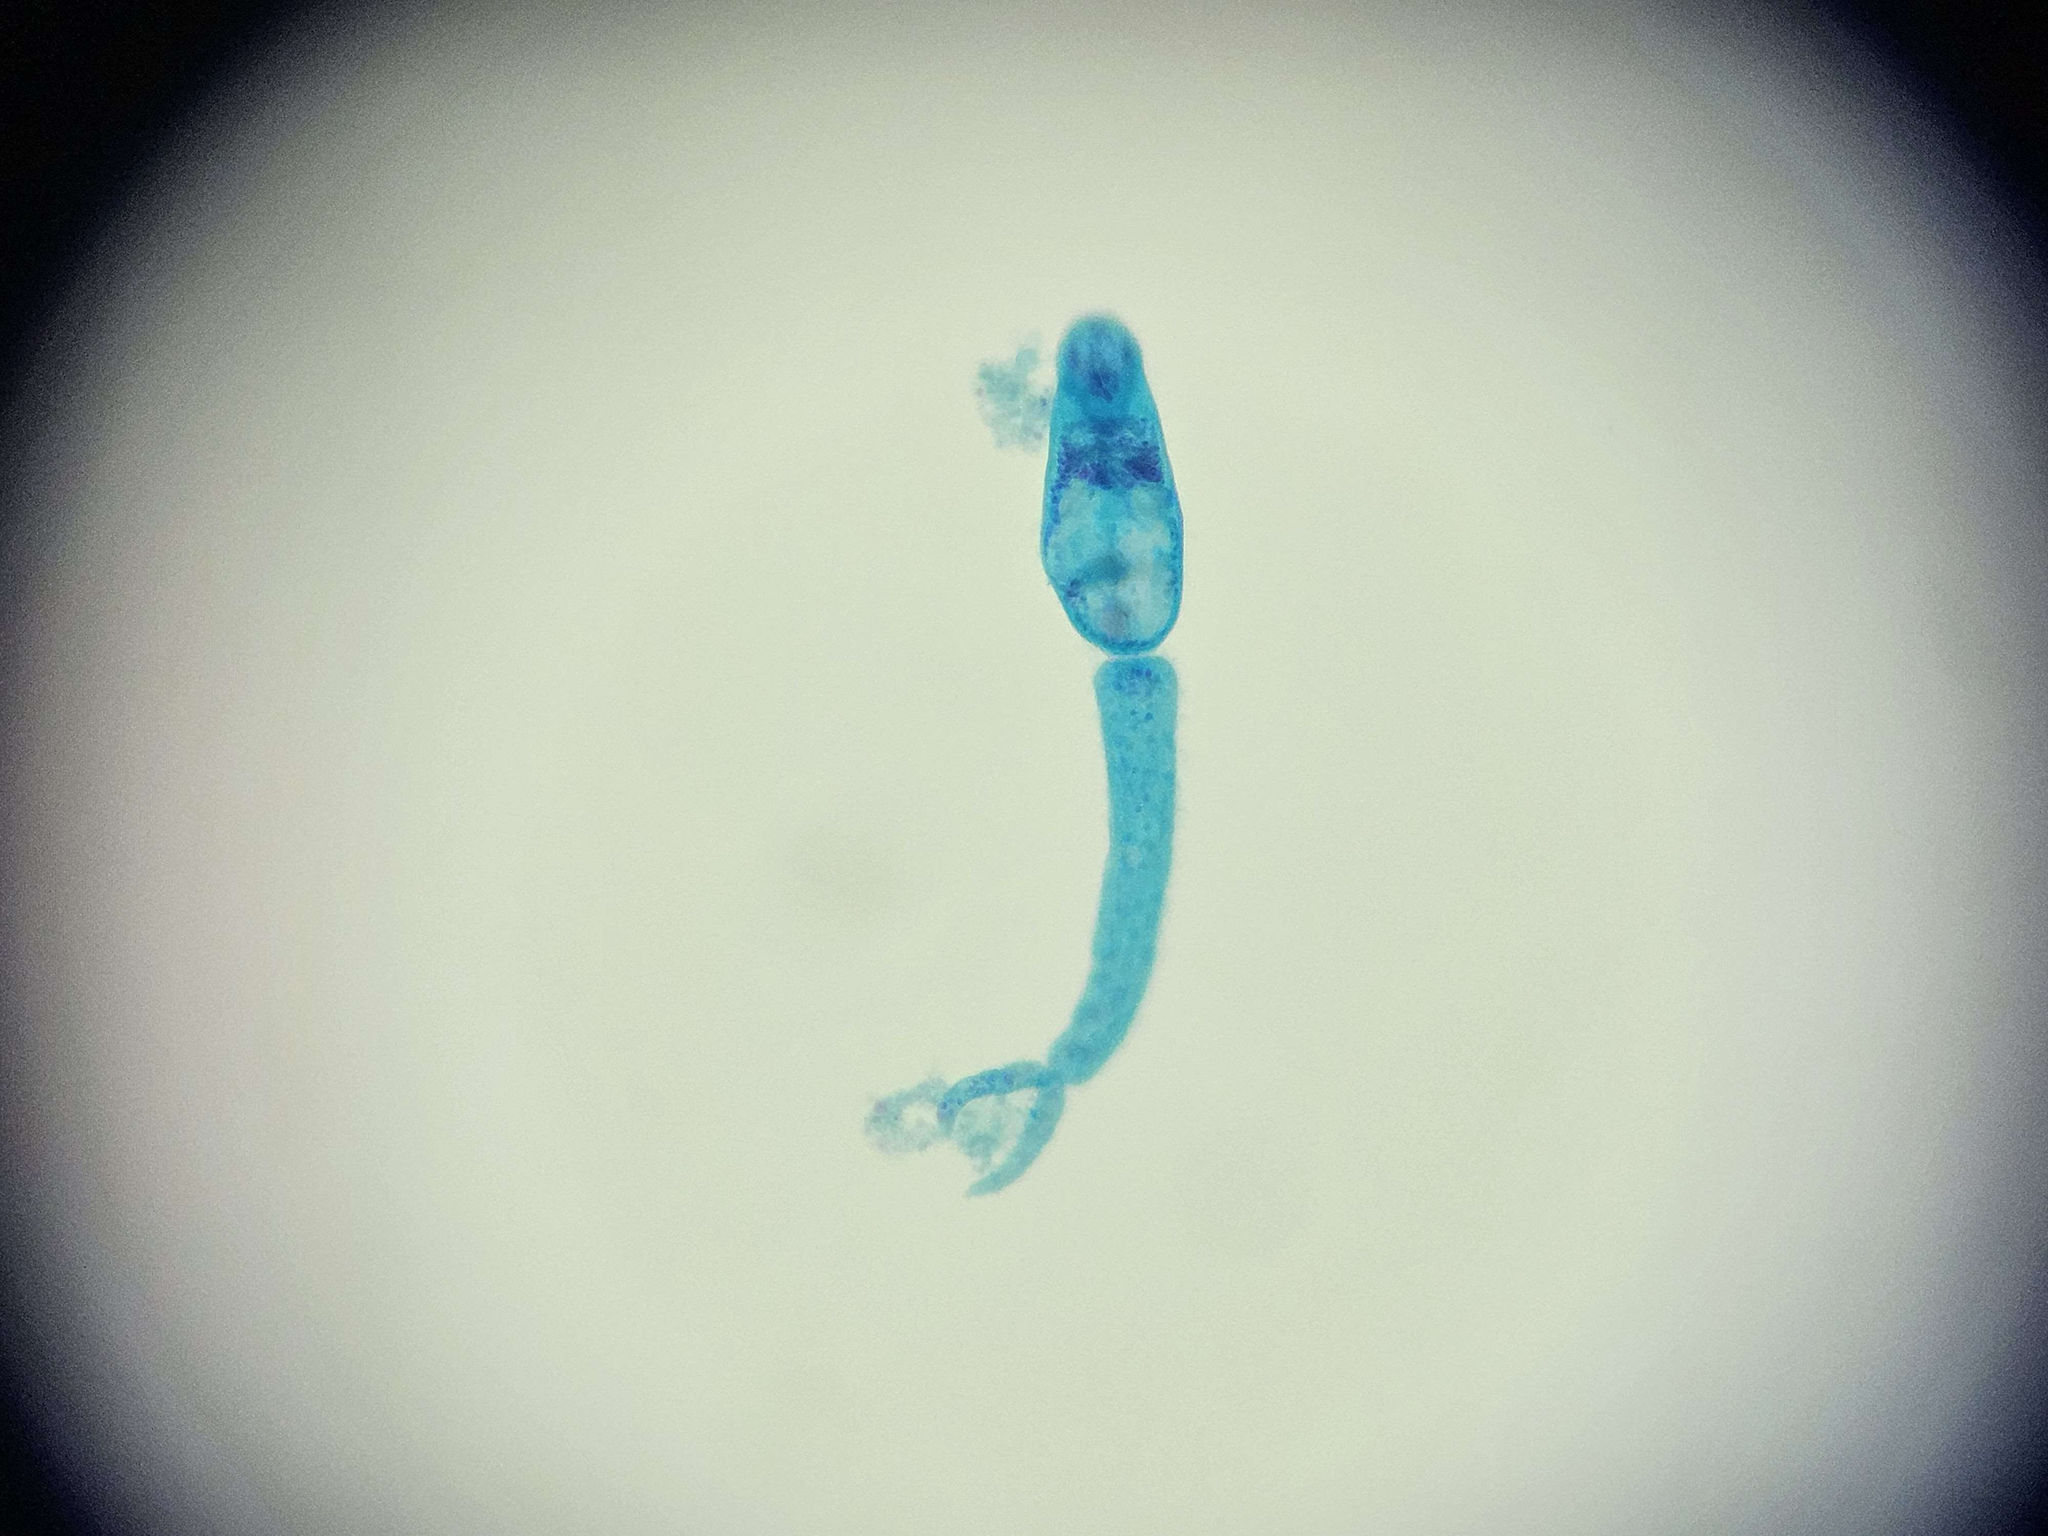

🪱🧱 Schistosoma mansoni (Cerkaria)

🧩🦠 Organelle:

⚫️ - przyssawka gębowa

🟣 - gardziel;

🟤 - jelito;

🟡 - przyssawka brzuszna;

🔴 - wyrostek ogonowy.

😷❓ Parazytoza: Schistosomoza przewodu pokarmowego

🔴 - wyrostek ogonowy;

️⚪ - widełki.